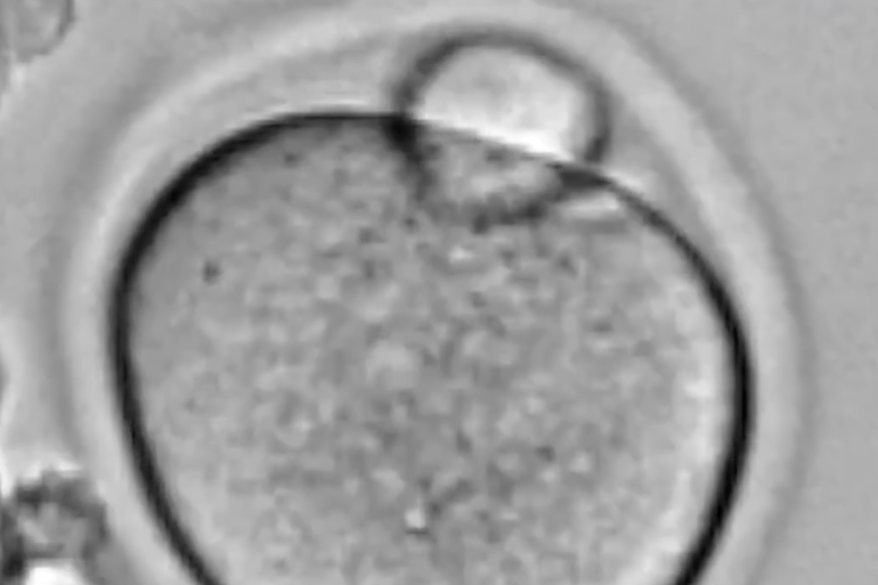

VIDEO Le ovaie stampate in 3D contro l’infertilità

Alla Northwestern University le prime ovaie stampate in 3D hanno hanno permesso di ripristinare l'equilibrio ormonale dei roditori

Ovaie stampate in 3D per restituire la fertilità a topi sterili e magari applicare la stessa tecnologia agli esseri umani, riportando nella norma anche l'equilibrio ormonale per la riproduzione. Dietro la studio ci sono i ricercatori coordinati da Ramile Shah e Teresa Woodruff, della Northwestern University. L'obiettivo è restituire la fertilità alle donne che l'hanno perduta dopo la chemioterapia.

Strato dopo strato, i ricercatori hanno stampato una struttura che imita quella delle ovaie: è una sorta di impalcatura costellata di pori, nei quali sono state alloggiate le cellule uovo immature e quelle che le nutrono e le proteggono, cioè i follicoli ovarici.

Una volta impiantata nei topi, la struttura si è integrata con gli altri tessuti, si sono formati i vasi sanguigni e sono maturati gli ovuli. In questo modo le ovaie stampate in 3D hanno ripristinato la funzione ormonale ideale per la riproduzione, che ha permesso il concepimento e la nascita dei cuccioli, nonché l'allattamento. La ricerca, ha rilevato Woodruff, mostra che queste ovaie hanno "una funzione a lungo termine e duratura". Il prossimo passo sarà adattarle, nella struttura e nelle dimensioni, ai follicoli ovarici umani.